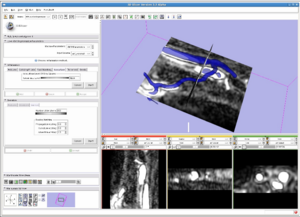

- 3.26 Panorama Ultrasound for Navigation and Guidance of Epidural Anesthesia